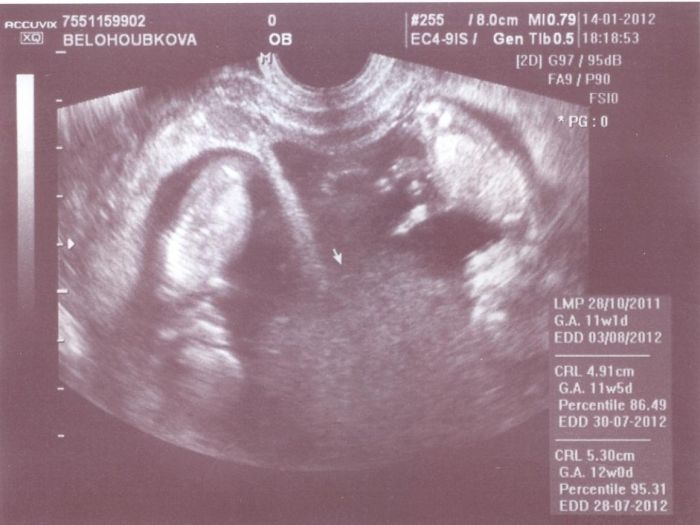

Ahoj holky taky čekáme dvojčátka . podle UTZ ve 20tt budeme mít kluka a holku ted jsem ve 29+2tt a čeká mě druhý velký utz

- fotečka je z 11+1tt to mi poprvé řekli že budeme mít dvojčátka